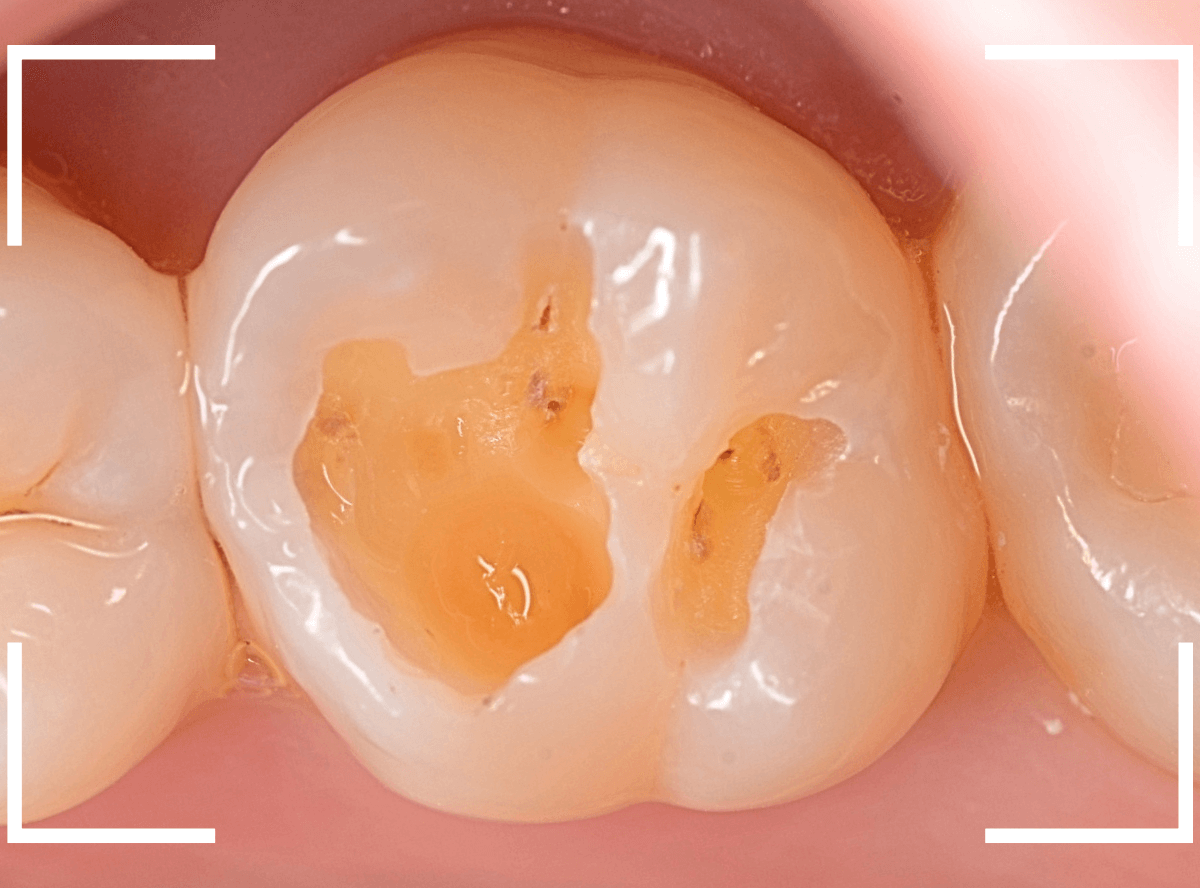

Case.10 レントゲンに写らない側面の虫歯を、少しずつ削って調べる

こちらも、虫歯が歯のあちこちで進行してしまっている患者さんのケースです。

特に側面の虫歯が深そうです。

側面にできた虫歯はレントゲン写真では診断しづらくやっかいです。

今回は「見るからに深そう」ですが。

さすがにレントゲン写真でも虫歯がありそうな事は確認できますが、実際にどうなってるのかはあまりはっきりわかりません。

少しずつ虫歯を除去していきます。

歯の側面から、手前の歯までつながった虫歯になっていました。

手前の歯までの虫歯を除去しました。

歯の後ろ側の側面も、大きな虫歯になっていますので、処置します。

隣の歯との間(隣接面)は、中で虫歯が広く進んでることが多いです。

結局、前後の歯に渡る広い虫歯でした。

レントゲン写真だけでは、ここまでの虫歯は判断できませんでした。